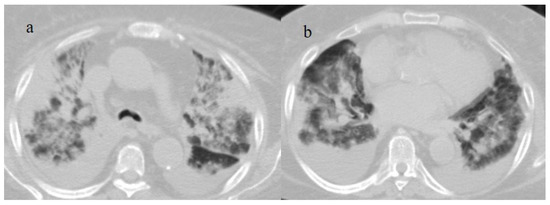

- Bonaffini, P.A.; Franco, P.N.; Bonanomi, A.; Giaccherini, C.; Valle, C.; Marra, P.; Norsa, L.; Marchetti, M.; Falanga, A.; Sironi, S. Ischemic and hemorrhagic abdominal complications in COVID-19 patients: Experience from the first Italian wave. Eur. J. Med. Res. 2022, 27, 1–9. [Google Scholar] [CrossRef]

- Fathy, A.; Rizk, A.; Elnekeidy, A.; Gharraf, H.S.; Abdelgawad, M.S.; Samir, A. Imaging of COVID-19 vasculopathy from head to toe: Egyptian collective experience after 2 years of the pandemic. Egypt. J. Radiol. Nucl. Med. 2022, 53, 1–21. [Google Scholar] [CrossRef]

- Evrev, D.; Sekulovski, M.; Gulinac, M.; Dobrev, H.; Velikova, T.; Hadjidekov, G. Retroperitoneal and abdominal bleeding in anticoagulated COVID-19 hospitalized patients: Case series and brief literature abdominal bleeding in anticoagulated COVID-19 hospitalized patients: Case series and brief literature review. World J. Clin. Cases 2023, 11, 1528–1548. [Google Scholar] [CrossRef] [PubMed]

- Sposato, B.; Croci, L.; Di Tomassi, M.; Puttini, C.; Olivieri, C.; Alessandri, M.; Ronchi, M.C.; Donati, E.; Garcea, A.; Brazzi, A.; et al. Spontaneous abdominal bleeding associated with SARS-CoV-2 infection: Causality or coincidence? Acta Biomed. 2021, 92, e2021199. [Google Scholar] [PubMed]

- Mahmoudabadi, H.Z.; Hadadi, A.; Fattahi, M.R.; Kafan, S.; Ashouri, M.; Allahbeigi, R.; Hajebi, R. Rectus Sheath Hematoma in COVID-19 Patients as a Mortal Complication: A Retrospective Report. Int. J. Clin. Pract. 2022, 2022, 7436827. [Google Scholar] [CrossRef]

- Maruyama, S.; Wada, D.; Oishi, T.; Saito, F.; Yoshiya, K.; Nakamori, Y.; Kuwagata, Y. A descriptive study of abdominal complications in patients with mild COVID-19 presenting to the emergency department: A single-center experience in Japan during the omicron variant phase. BMC Gastroenterol. 2023, 23, 43. [Google Scholar] [CrossRef]

- Mahboubi-Fooladi, Z.; Arabi, K.P.; Khazaei, M.; Nekooghadam, S.; Shadbakht, B.; Moharamzad, Y.; Taheri, M.S. Parenteral Anticoagulation and Retroperitoneal Hemorrhage in COVID-19: Case Report of Five Patients. SN ComPract. Clin. Med. 2021, 3, 2005–2010. [Google Scholar] [CrossRef] [PubMed]

- Dubovský, M.; Hajská, M.; Panyko, A.; Vician, M. Severe Retroperitoneal Hemorrhage in a COVID-19 Patient on a Therapeutic Dose of Low Molecular Weight Heparin: A Case Report. Cureus 2022, 14, 26275. [Google Scholar] [CrossRef] [PubMed]

- Yeoh, W.C.; Lee, K.T.; Zainul, N.H.; Alwi, S.B.S.; Low, L.L. Spontaneous retroperitoneal hematoma: A rare bleeding occurrence in COVID-19. Oxf. Med. Case Rep. 2021, 2021, omab081. [Google Scholar] [CrossRef] [PubMed]

- Shah, M.; Colombo, J.P.; Chandna, S.; Rana, H. Life-Threatening Retroperitoneal Hematoma in a Patient with COVID-19. Case Rep. Hematol. 2021, 2021, e8774010. [Google Scholar] [CrossRef]

- Belfiore, M.P.; Russo, G.M.; Gallo, L.; Atripaldi, U.; Tamburrini, S.; Caliendo, V.; Impieri, L.; Del Canto, M.T.; Ciani, G.; Parrella, P.; et al. Secondary Complications in COVID-19 Patients: A Case Series. Tomography 2022, 8, 1836–1850. [Google Scholar] [CrossRef]